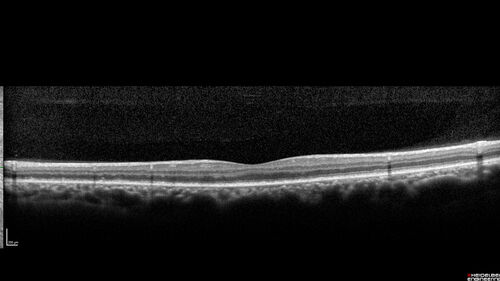

Ocular Lymphoma - Initially presented like auto-immune retinopathy

43 year old man: initial presentation - The vision in the left eye is blurry and opaque for about 2 weeks.  In the central of the vision, when he covers the right eye, in the center of the left eye there is a film with a light in the middle.  This has never happened before.  He has not been sick for the last few months.  A few weeks ago he saw waves on the floor when looking down but that has gone away.  Since the vision loss started the vision has not changed much.  The central vision is not getting better.

VA improved over 2 months to normal.  Then the patient had 2 more episodes of self-limited vision loss (no treatment).  Then 2 years later he presented with a diagnosis of CNS lymphoma and later developed subretinal deposits (last images)